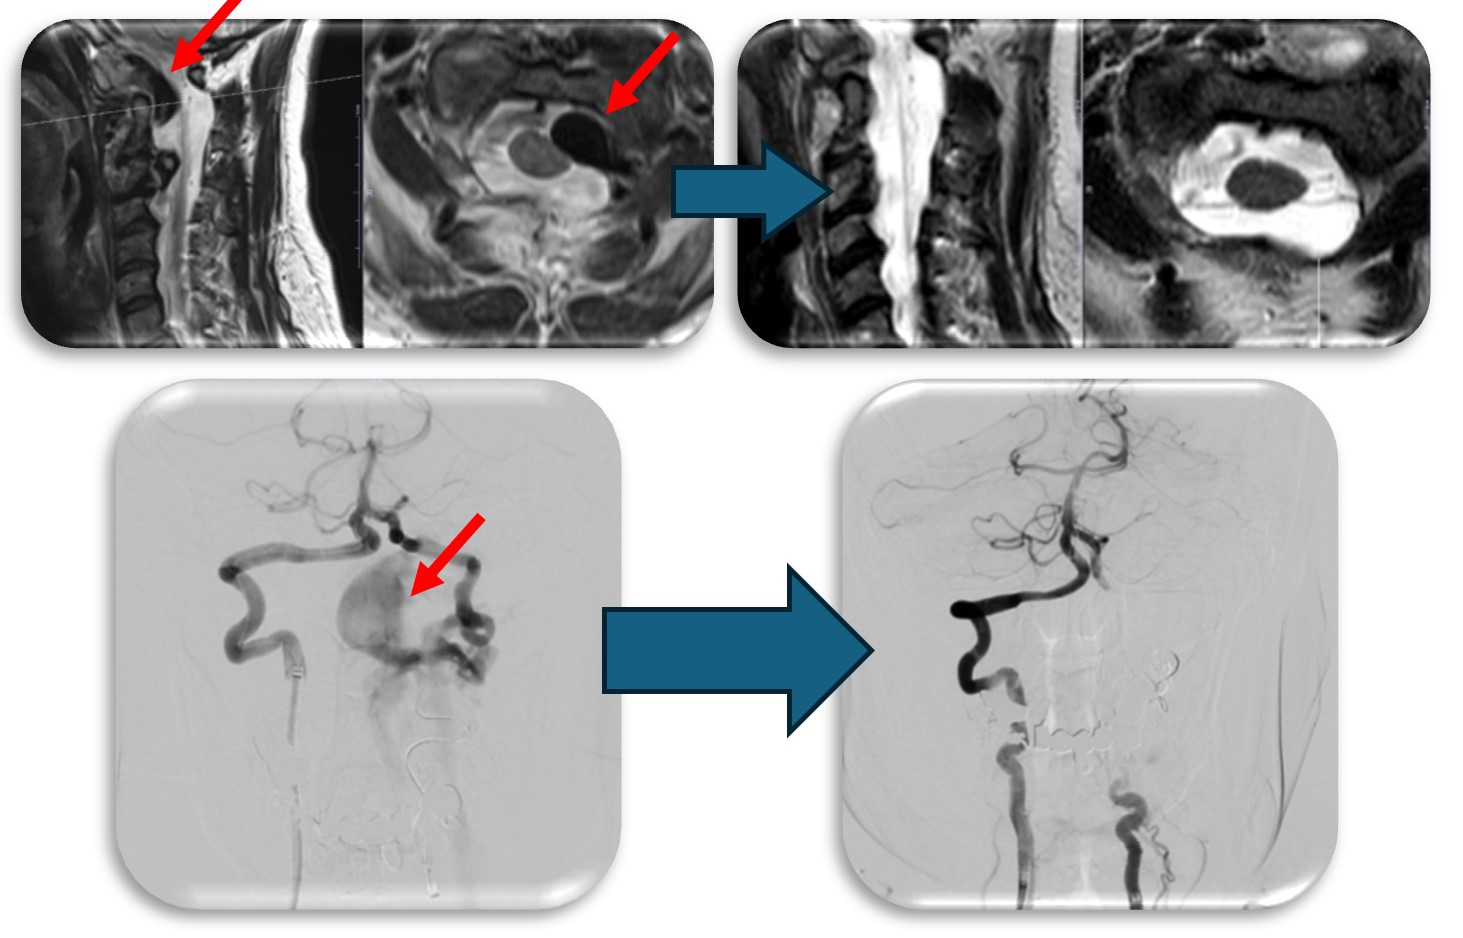

(代表例②)

頚部にできた血管奇形の症例です。当初脊髄腫瘍という話で紹介された症例でしたが、巨大な血管奇形でした(赤矢印)。椎骨動脈と脊柱管内の静脈に異常なシャントが原因で巨大な静脈瘤を呈し、それが脊髄を圧迫し神経症状を来していました。この症例はもともと神経繊維腫症1型という遺伝子疾患の既往があったのですが、まれに頚椎や頚椎周囲の血管に奇形を呈することがあります。このような症例は外科的治療は危険性が非常に高く、血管内治療で治療しました。なお、この症例は環軸椎亜脱臼も呈しており今後時期を診て脊椎手術も行う予定です。